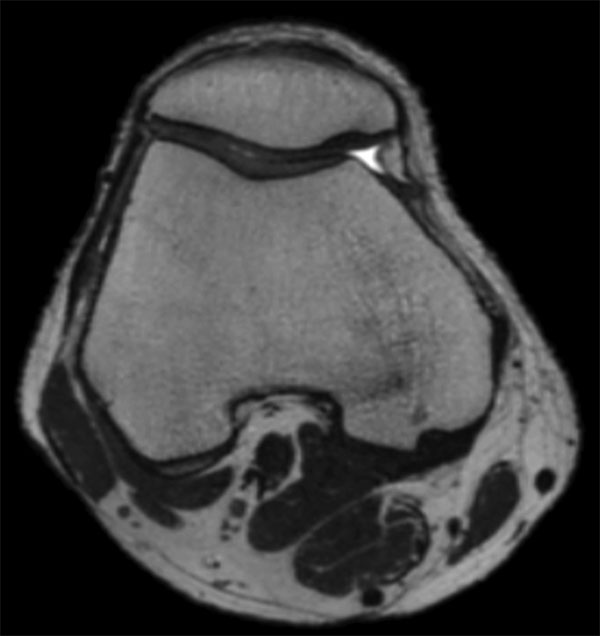

Comprehensive 3D knee imaging with MSK VIEW